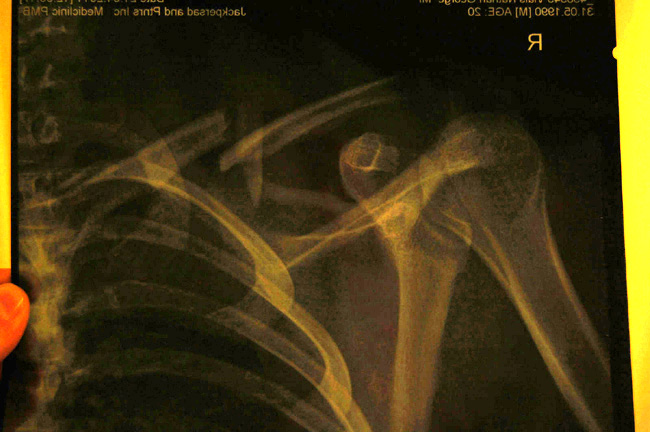

First run down on Thursday Nathan set off in front of me and I cruised down the track having a look and pushing back up to do some jumps. I got about 30 maybe 40 seconds into the track when I saw some yellow flags. I rode past slowly, and recognised the bike on the floor so I stopped to see who it was, hoping they were okay. I was gutted to see it was Nathan on the side of the track in a lot of pain having broken his collar bone. He had come into a dusty section where you skirt around a bank on a ledge and his front wheel had washed out, smashing into some rocks and the catch netting. It was a really unlucky crash, especially as he had missed last year’s WC season having broken his other collar bone! So now Harry and Nathan were broken, and there was only me left!

After practise we went to the hospital to see Nathan who was looking pretty sore and was going to have an op that night. His x-ray was gnarly; he’d smashed his collar bone into 3 sections and needed plating back together. Jess Stone was also at the hospital having separated her AC joint and torn some ligaments (I think) crashing on a double I’d also chain ringed earlier that day!

Nathan’s collar bone in bits.